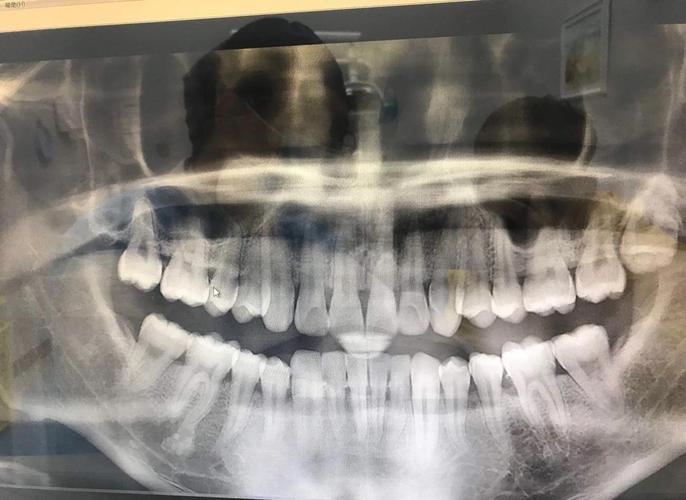

牙槽骨吸收在X光片(主要是根尖片或曲面断层片)上通常表现为以下特征:

- 最直观的表现: X光片上可以看到牙齿根尖周围的牙槽骨(硬骨板)的高度比治疗前或健康邻牙低。

- 骨皮质变薄或模糊: 牙根周围的白色致密骨线(牙槽骨的骨皮质)变得不清晰、变薄甚至中断。

- 牙槽嵴顶高度下降: 牙龈缘对应位置的牙槽骨顶部(牙槽嵴顶)位置降低。

- 骨小梁结构稀疏: 牙槽骨内部的骨小梁(网状结构)变得稀疏、排列紊乱,透光度增加(在X光片上看起来更“黑”一些)。

- 骨透射影: 在吸收严重的区域,可能看到更明显的黑色透射影,表示骨量减少。

- 增宽: 在牙槽骨吸收区域,牙齿与牙槽骨之间的牙周膜间隙可能暂时性或持续性增宽,这通常表示牙齿在移动或受到轻微创伤,是正畸过程中常见的现象,但持续增宽或异常增宽可能提示问题。

- 模糊: 吸收区域的牙周膜间隙边界可能变得模糊不清。

(图片来源网络,侵删)- 牙根吸收: 虽然牙根吸收和牙槽骨吸收是两个概念,但严重的牙槽骨吸收有时会伴随或导致牙根吸收,X光片上可见牙根长度缩短或形态不规则。

骨皮质中断: 牙根外侧的骨皮质线出现中断或消失。

- X光片类型: 根尖片能更清晰地显示单颗牙齿周围的牙槽骨细节,是评估牙槽骨吸收最常用的影像学方法,曲面断层片可以同时显示全口牙槽骨情况,但单颗牙齿的细节不如根尖片清晰。